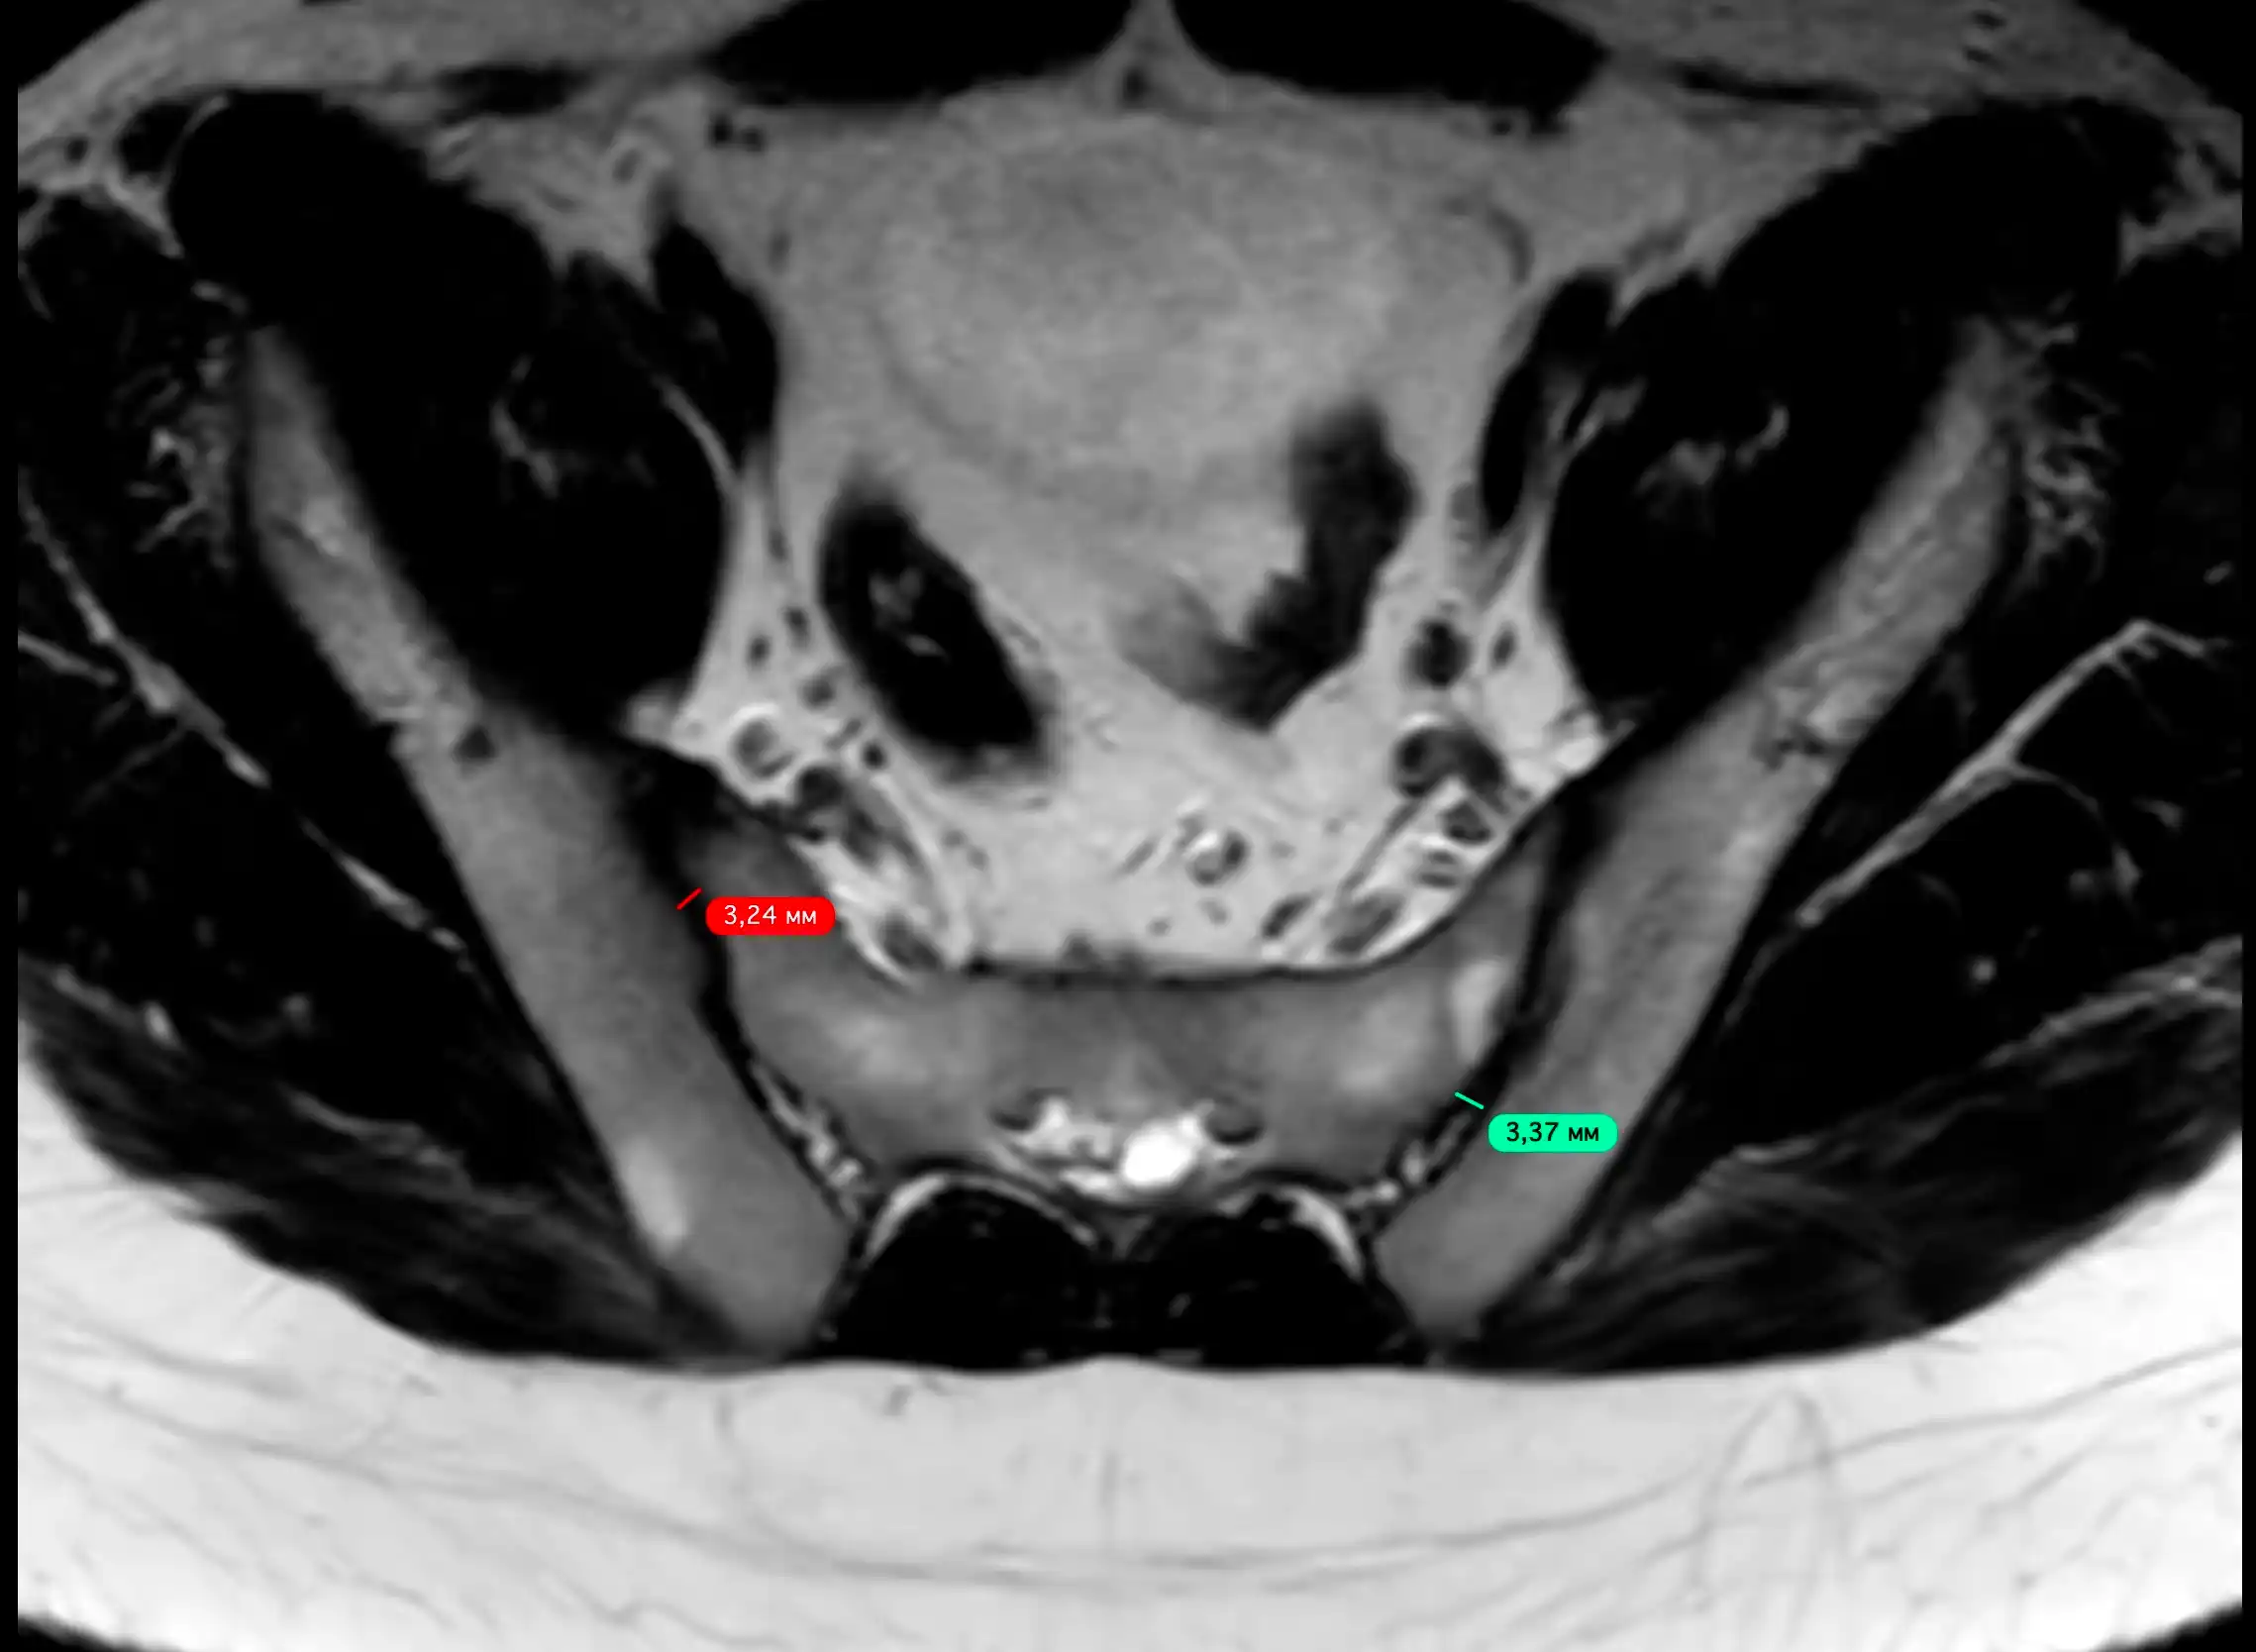

МРТ здухвинно-крижових сполучень (крижово-клубових суглобів) — це сучасний метод обстеження, який дозволяє детально оцінити стан суглобів між крижовою кісткою та клубовими кістками таза.

Магнітно-резонансна томографія є одним із найточніших методів виявлення запальних, дегенеративних та травматичних змін у цій ділянці. Дослідження проводиться без використання рентгенівського випромінювання.

Що показує МРТ крижово-клубових суглобів

МРТ дозволяє виявити:

- запалення суглобів (сакроілеїт)

- ранні прояви хвороби Бехтерєва

- дегенеративні зміни суглобів

- травматичні ушкодження

- пухлини та новоутворення

- набряк кісткового мозку

- зміни зв’язок і м’яких тканин